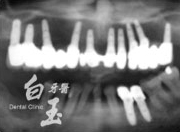

患者全口 X 光